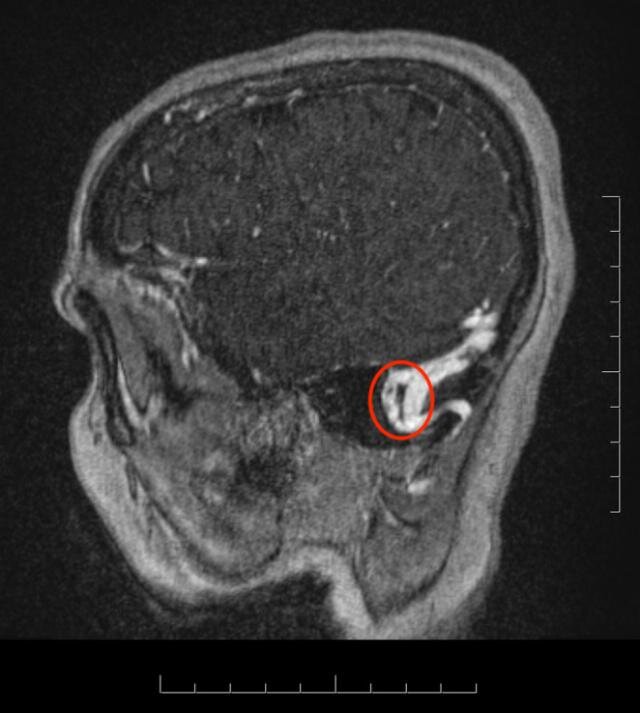

На МРТ с ангиографией и венографией: тромбоз левого сигмовидного синуса, частично пустое турецкое седло, заполнено ликвором. Двусторонний отек зрительного нерва, внутричерепная гипертензия.

Ответ невролога: перенесла инсульт на ногах примерно 7-8 месяцев назад. Лечения не получала. Экстренно госпитализирована в отделение неврологии.

Тромбоз синусов твердой мозговой оболочки редкая причина инсульта у женщин.